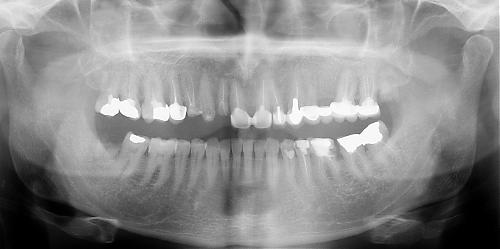

بودي ان استشيرك حول عمل التلبيسات لاسناني من نوع ان سيرام وماذا يتطلب عمله قبل المجيء الى عيادتكم حسب ماترونه مناسب وحسب الاشعة المرفقة لكم في هذه المشاركة

بالنسبة لحالتك أنت تحتاج لأكثر من ثمانية تلبيسات كما اشاهد من الصورة

ولكن كما أشاهد في الصورة يوجد لديك مشكلة في أحد الأسنان وهو الناب الموجدود جانب السن المكسور ( والذي لا أظن أنه بحاجة إلى قلع ) سنكشف عليه عندما تأتي إلى العيادة